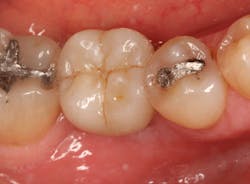

Stage II uncovering was performed five months following the initial surgery. A crestal incision was made toward the lingual ridge to split the keratinized gingiva, as that is where the keratinized gingiva had settled following surgery due to the coronal advancement of the buccal flap to obtain primary closure. The keratinized gingiva was buccally positioned, and a healing abutment was placed. The tissue was sutured with 4.0 chromic gut. This allowed the attached gingiva to heal on the buccal portion of the healing abutment and thus remain on the buccal portion of the final restoration. Final impressions were taken two weeks later, and the restoration was delivered thereafter.

The patient returned three and six months later for a postdelivery radiograph and healing check. The peri-implant tissues were healthy with no abnormal bleeding or probings. The patient reported high satisfaction with his new implant restoration.